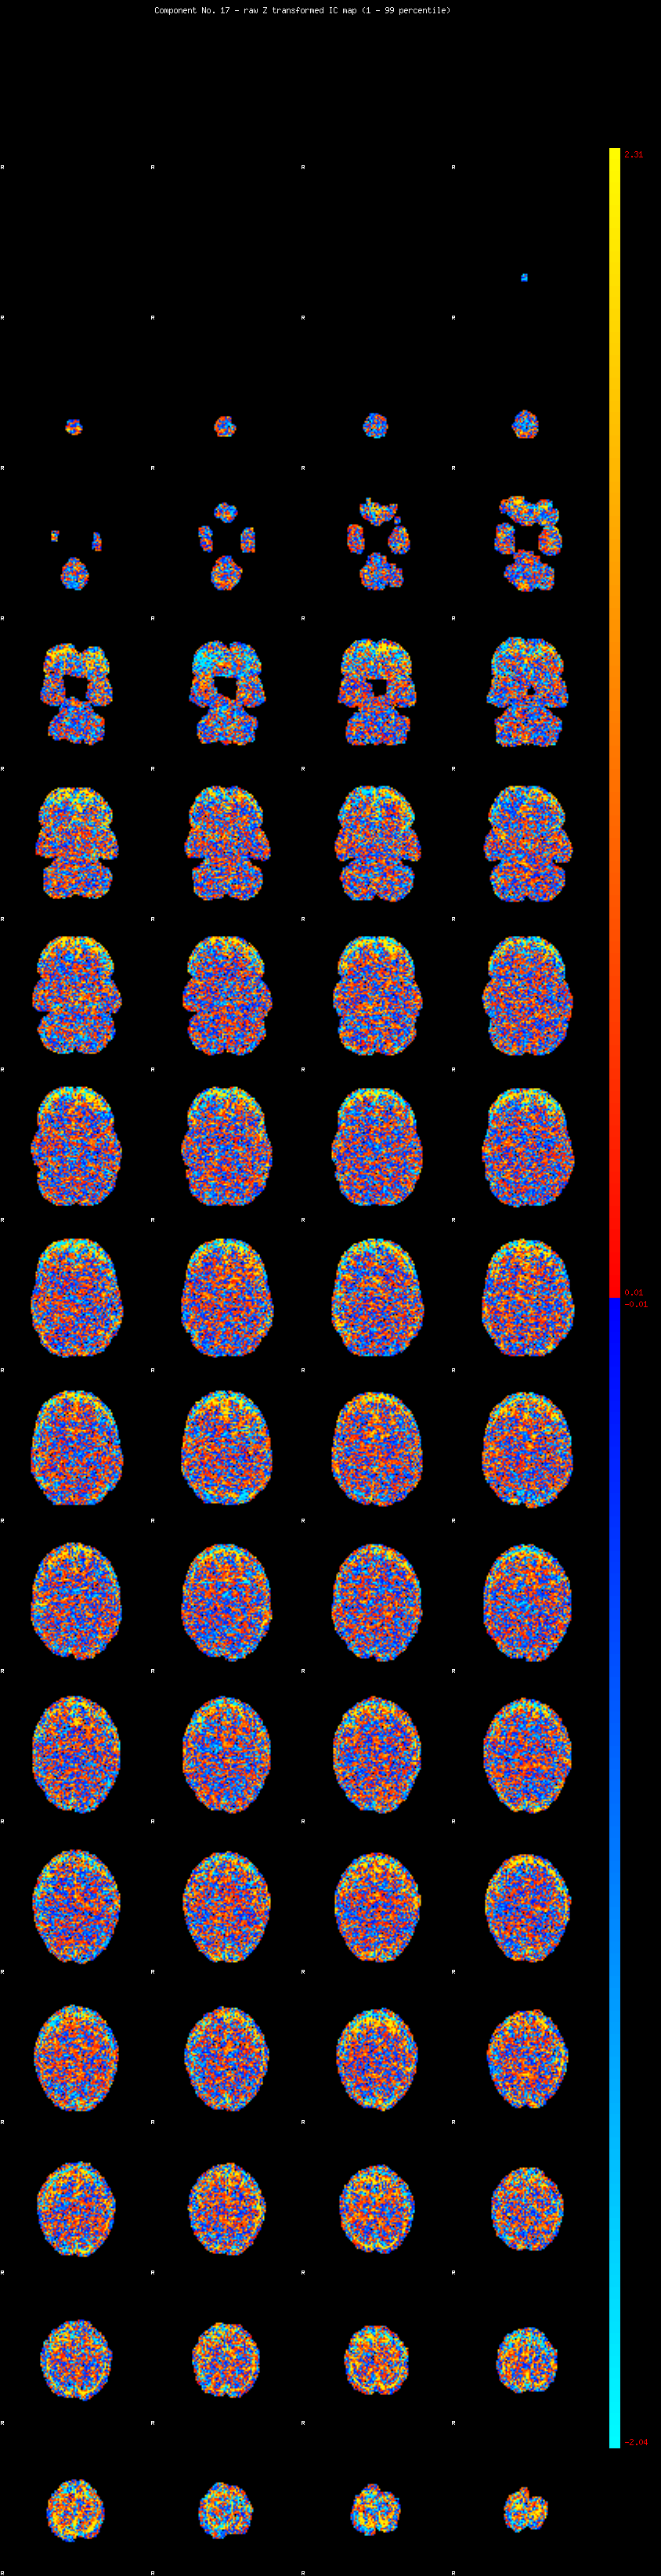

IC_17 Mixture Model fit

Means : -0.000000 2.557994 -2.398313

Vars : 1.000000 2.124937 1.708857

Prop. : 0.895122 0.064235 0.040643